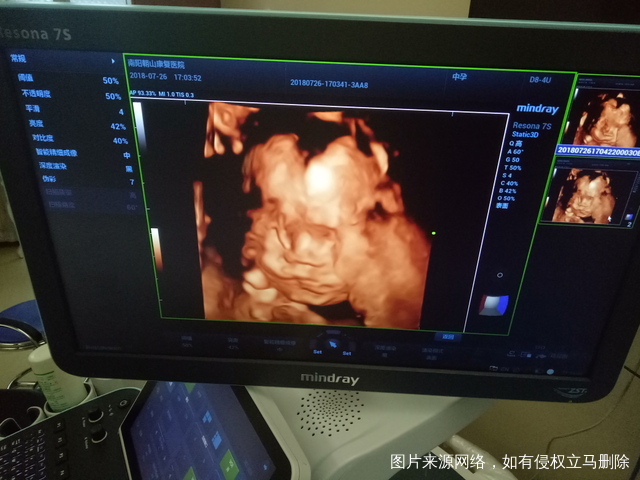

二胎四维图,大脸盘,大家猜猜是男是女,自己已知[开心]